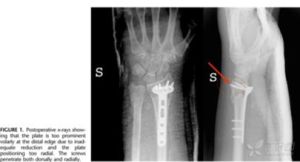

外傷史,局部腫脹,以腕背為主,向背側突出畸形,壓痛明顯,活動受限,可有骨擦感,側位X線片顯示骨折橈骨遠骨背側,包括關節面的1/3,多向背側及遠側移位,腕關節呈背側半脫位。

無相關實驗室檢查。側位X線片上可見骨折位於橈骨遠端背側,包括關節面的1/3,多向背側及遠側移位,腕關節呈背側半脫位狀態。